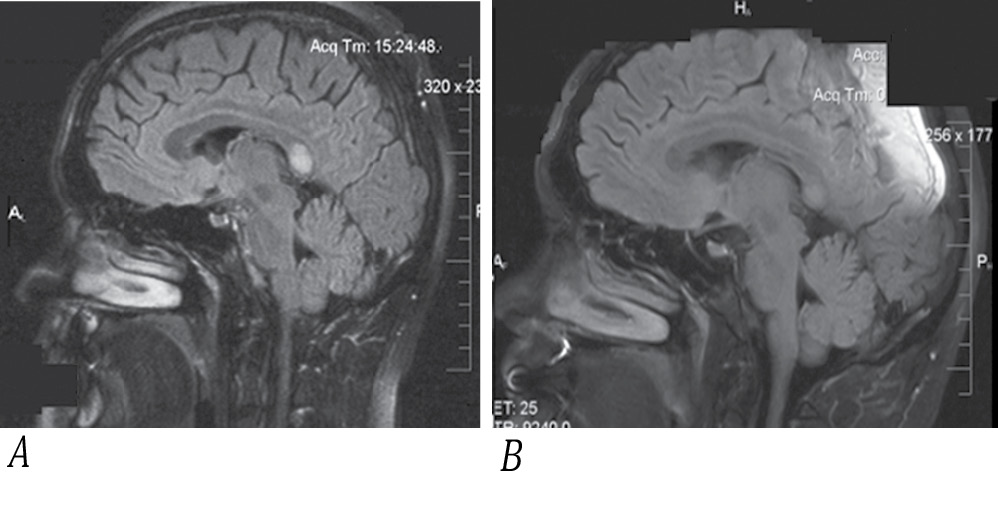

Рис. 4. МРТ пациента А. в режиме FLAIR, сагиттальный срез головного мозга.

А — 1-й день госпитализации, гиперинтенсивный очаг в ВМТ; В — 13-й день госпитализации, снижение интенсивности очага.

Fig. 4. Sagittal brain FLAIR MRI of рatient A.

A: day 1 of hospitalization; hyperintense splenial lesion; B: day 13 of hospitalization, decreased intensity of the lesion.